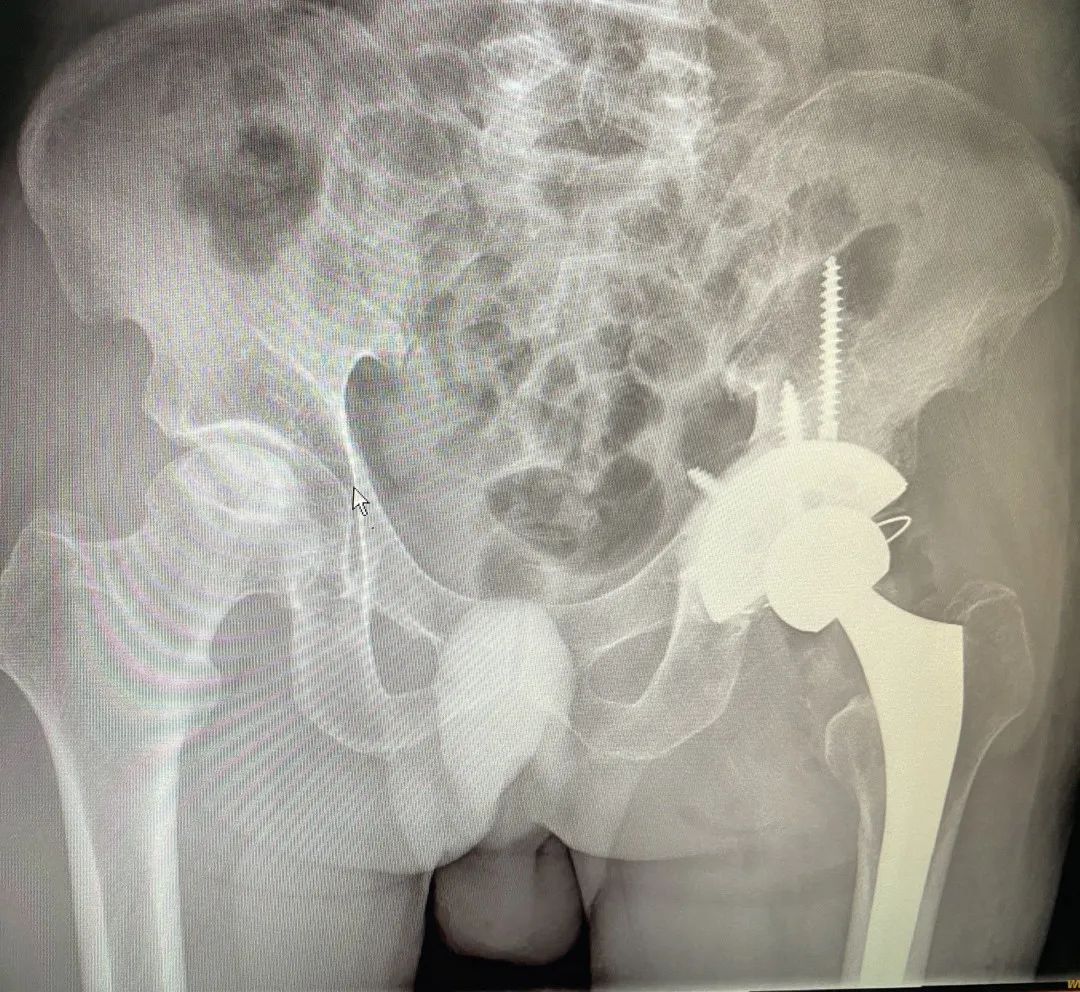

术后